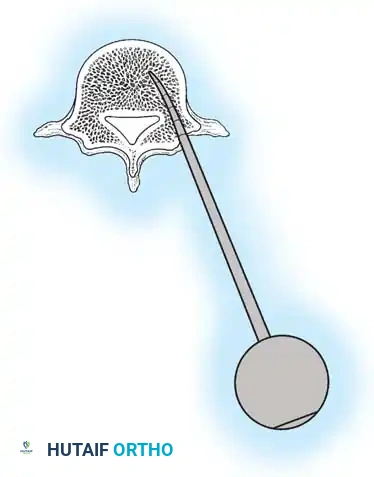

The Hall Technique

The Hall technique offers an alternative method for facet obliteration and grafting, particularly useful in rigid deformities.

Fig. 38-28: The Hall technique of facet fusion, involving sharp excision of the inferior facet and trough creation.

- Sharply amputate the inferior articular facet with a gouge and remove the bone fragment entirely. This exposes the cartilage of the superior facet.

- Remove the exposed cartilage completely with a sharp curet.

- Create a bleeding trough by removing the outer cortex of the superior facet.

- Impact cancellous bone grafts directly into this vascularized trough.

- Complete the procedure with global decortication of the posterior elements.